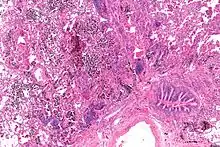

Micrograph showing a pulmonary hemorrhage. H&E stain.

Pulmonary hemorrhage (or pulmonary haemorrhage) is an acute bleeding from the lung, from the upper respiratory tract and the trachea, and the pulmonary alveoli. When evident clinically, the condition is usually massive.[1] The onset of pulmonary hemorrhage is characterized by a cough productive of blood (hemoptysis) and worsening of oxygenation leading to cyanosis.[1] Treatment should be immediate and should include tracheal suction, oxygen, positive pressure ventilation, and correction of underlying abnormalities such as disorders of coagulation. A blood transfusion may be necessary.[1]